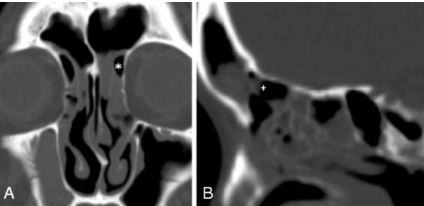

_____ may cause mechanical obstruction to frontal sinus drainage and lead to frontal sinusitis